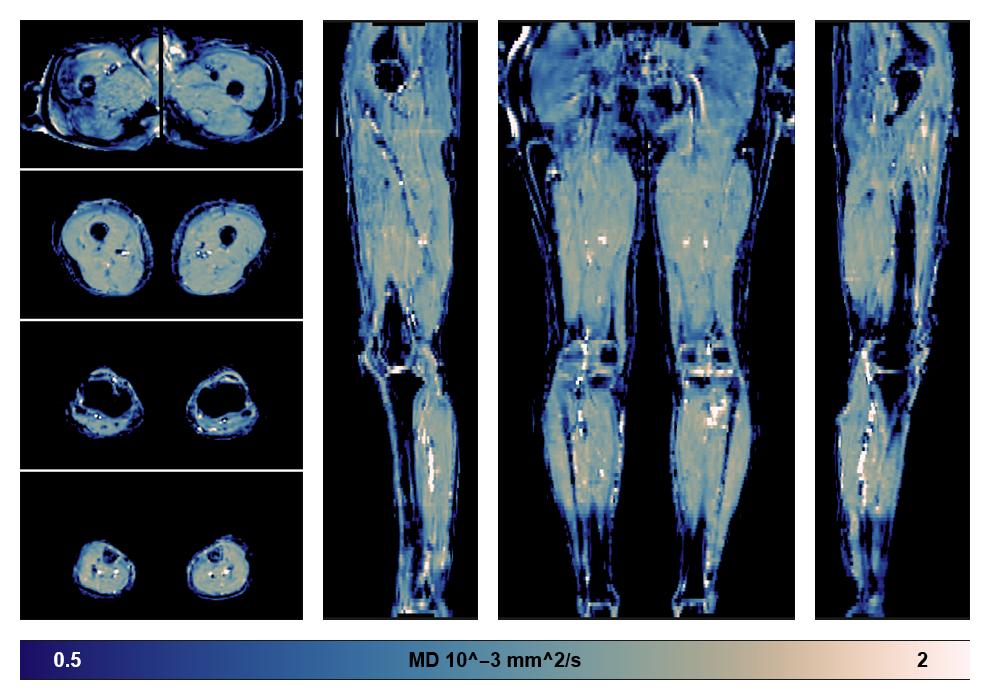

• Mean diffusivity

IVIM corrected whole leg muscle mean diffusivity obtained from diffusion tensor imaging.